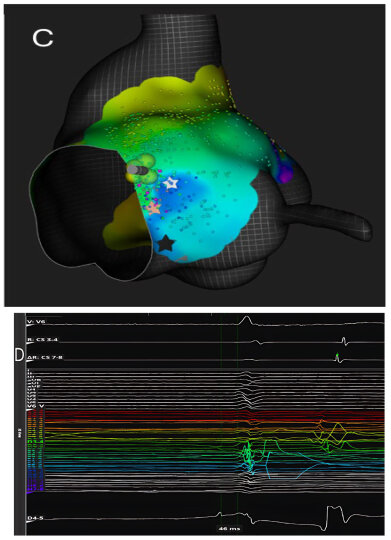

Beyond technical precision, the ability to localize the compact AV node and its extensions carries major clinical implications. Targeted ablation within the defined nodal zone reduces the risk of His bundle injury, preserves intrinsic junctional escape rhythm, and minimizes the occurrence of proarrhythmic scar formation or QRS widening (Figure 5).

Figure 5. Junctional escape rhythm at the end of radiofrequency delivery. Junctional escape rhythm appearing immediately after cessation of radiofrequency (RF) energy delivery at the anatomical site of the atrioventricular node, spatially distinct from the His bundle. The ablation catheter records an atrial electrogram occurring later than that recorded by both right- and left-sided His bundle catheters, confirming its nodal—not Hisian—location. The emergence of a stable junctional rhythm following energy delivery indicates successful nodal-level block with preservation of a physiological escape focus. Abbreviations: Abl = ablation catheter; CS = coronary sinus; His = His bundle recording.